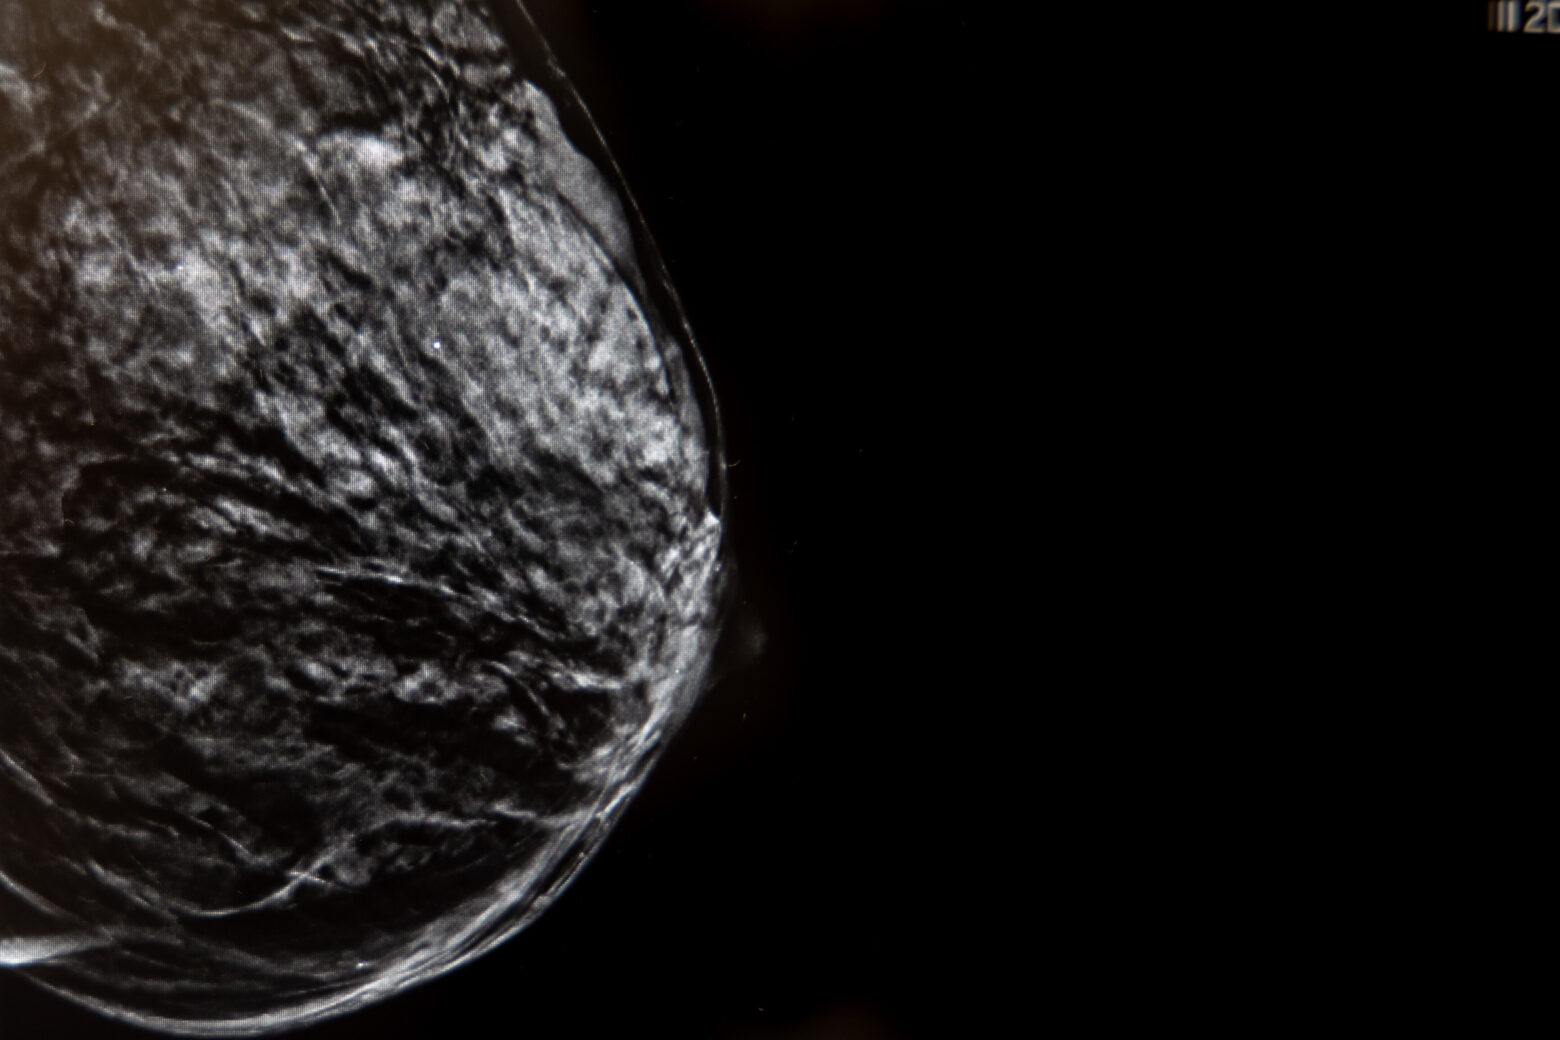

Uno de los mayores avances en el diagnóstico mamario es la imagen 3D (Tomosíntesis) que consiste en la adquisición de imágenes de baja dosis de radiación.